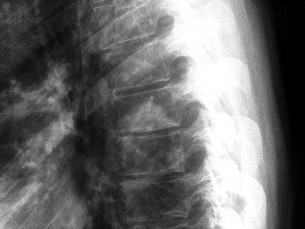

A 65-year-old male presents with classic symptoms of neurogenic claudication. He reports bilateral leg pain and fatigue that worsens with walking but is reliably relieved by leaning forward onto a shopping cart. In the pathogenesis of degenerative lumbar spinal stenosis, which structure is primarily responsible for dynamic central canal compression during spinal extension?

Correct Answer: Ligamentum flavum

Explanation:

In degenerative lumbar spinal stenosis, extension of the spine decreases the sagittal diameter of the canal because the ligamentum flavum buckles inward (shingling), dynamically compressing the thecal sac. Flexion of the spine pulls the ligamentum flavum taut, increasing the available canal space and alleviating neurogenic claudication symptoms. Hypertrophic ligamentum flavum is a major structural contributor to central stenosis.